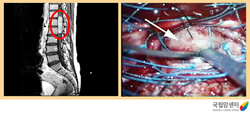

척수종양의 자기공명영상촬영(MRI) 및 척수종양 수술 장면

2009.08.21